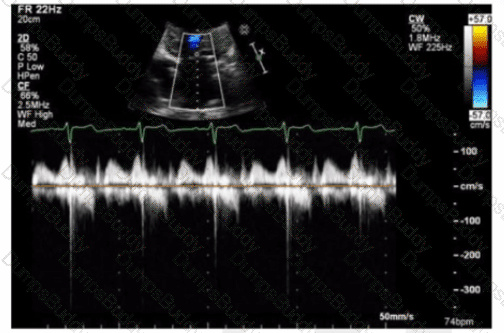

Which next step is appropriate after obtaining the Doppler signal in this image?